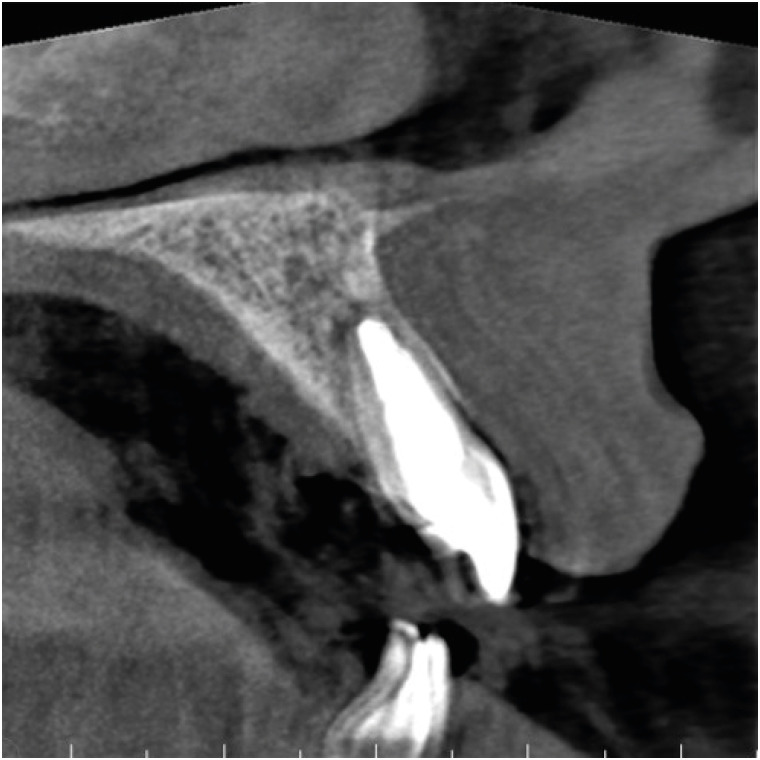

Figure 3

Cone-beam computed tomography image after the establishment of the apical mineral trioxide aggregate plug.

The working length was established with an electronic apex locator (Root ZX, J. Morita Corp., Tokyo, Japan) and confirmed via radiography. The canal was subjected to instrumentation only with NiTi files (K-File Nitiflex, Dentsply-Maillefer, Ballaigues, Switzerland), stainless steel hand files (K-File, Dentsply-Maillefer), and Hedstrom files (ReadySteel, Dentsply-Maillefer). The last instrument used for apical preparation was a size 120 file, and at that point a definite apical stop could be established. The site was irrigated with copious amounts of 5% sodium hypochlorite. At the time of drying, the electronic apex locator, the hand files, and the paper points indicated no sign of perforation. At the most apical part of the resorption defect, the root canal appeared extremely thin; thus, the use of warm gutta-percha for obturation was deemed risky and difficult to control. An approximately 4- to 5-mm-thick mineral trioxide aggregate (MTA) plug (MTA+, CERKAMED Medical Company, Stalowa Wola, Poland) was made to establish a proper apical barrier without error in the affected apical part (Figure 3). The MTA was covered with a moist cotton pellet, and the tooth was temporized with Cavit W filling material (3M ESPE, Seefeld, Germany) for 48 hours. At the next appointment, the root canal was adhesively treated with a dual-cure self-etch adhesive system (Gradia Core Self-Etching Bond, GC Europe, Leuven, Belgium) and was filled with SFRC (EverX Posterior, GC Europe) according to the Bioblock technique [15] to the point of the root canal orifice. During this procedure, an approximately 4-mm-thick increment of SFRC material was placed in the root canal and applied to the most apical part to make contact with the MTA plug. This can be accomplished by pressing alternately with any small-headed microbrush and a periodontal probe or plugger. After the first layer appeared to be in position, a light-transmitting FRC post (1.4 mm GC Fiber Post, GC Europe) was inserted into the canal to facilitate the transmission of the light to the apically-positioned layers. The light-transmitting post was withdrawn to 0.5–1 mm from the surface of the uncured SFRC layer so as not to directly contact it. The first layer of SFRC was light-cured through the post for 80 seconds using a light source with an average power density of 900 mW/cm2. This was continued to the level of the cemento-enamel junction. After the root canal was filled to that level, the coronal portion of the tooth was internally bleached several times with sodium perborate (made by the pharmacy of the University of Szeged) mixed with distilled water at a ratio of 2:1 (g/mL) and covered with glass ionomer filling (Equia Fore, GC Europe). After the desired color was reached, the coronal cavity and the SFRC material in the orifice were refreshed with a diamond bur, adhesively treated (G-premio Bond, GC Europe), and restored with SFRC and a 2-mm-thick composite covering on the palatal aspect (G-aenial Anterior, GC Europe) (Figure 4).